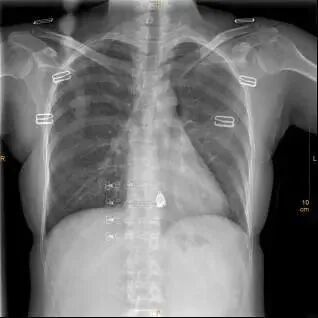

这是一张标准胸片

一张合格的胸片是不允许有任何体外异物的,因为任何异物的存在都会影响诊断。